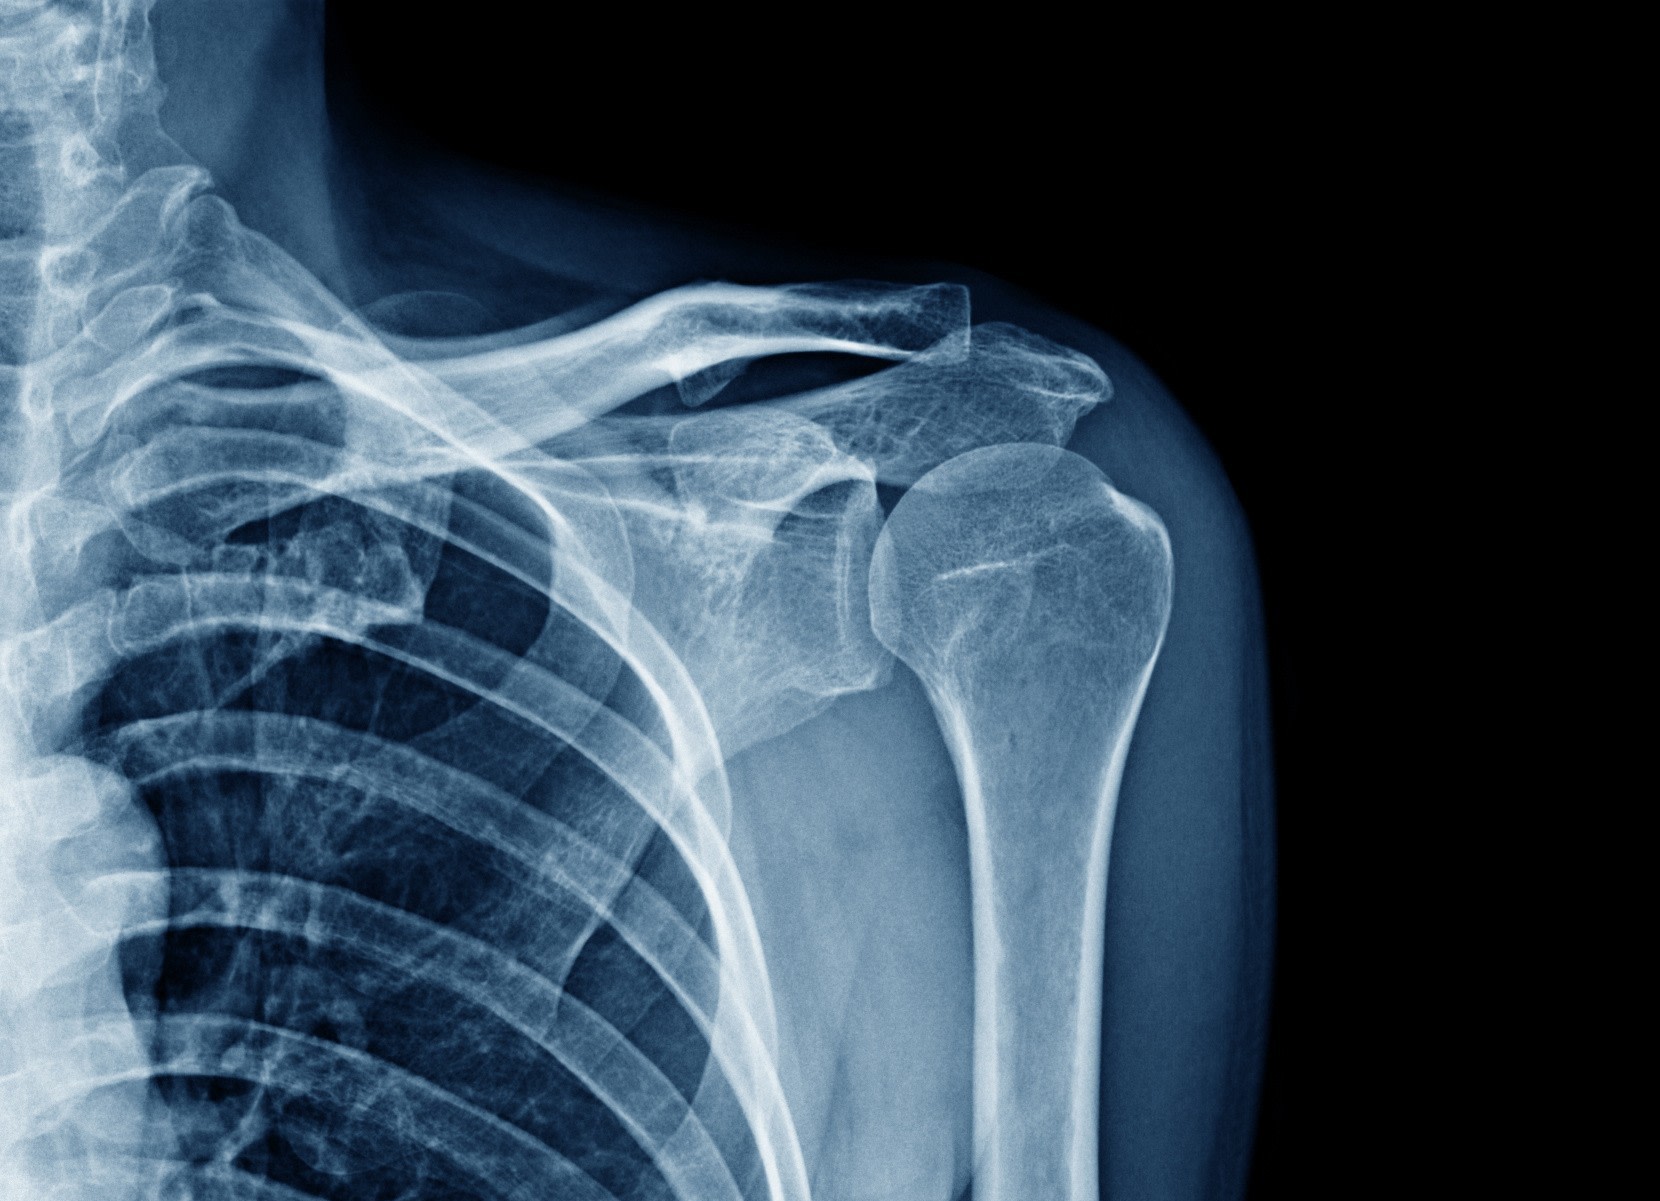

La Rupture du tendon long du biceps

La rupture provoque souvent une douleur brutale, parfois un “clac”, puis une déformation avec boule du biceps qui descend. La tendinite donne surtout des douleurs à l’effort sans déformation du muscle.